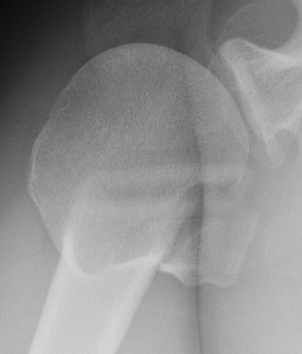

Isolated lesser tuberosity fractures in adults

- often associated with posterior shoulder dislocation

Traumatic avulsion of the lesser tuberosity and subscapularis insertion

- frequently missed on xray

- sensitivity of xray 16%

Lesser tuberosity can become overgrown